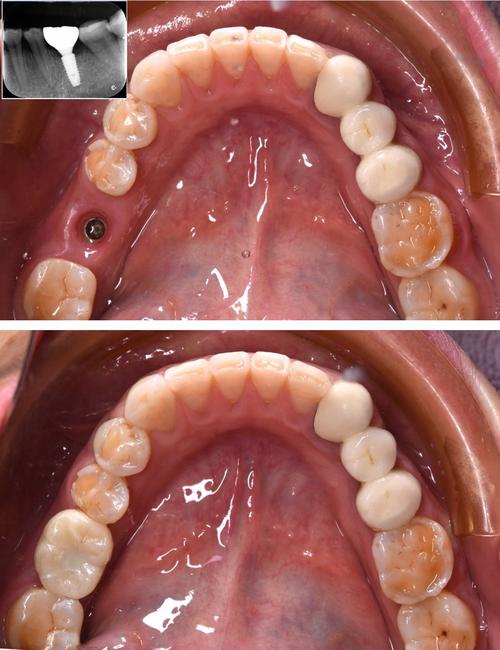

- 即刻种植:在拔牙后立即植入种植体,此时种植体位于拔牙窝内,需严格把控拔牙窝形态与种植体匹配度,避免唇侧骨壁穿孔。